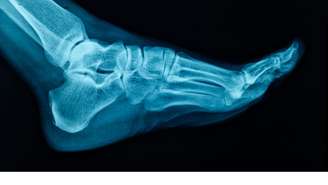

As intervenções cirúrgicas na região do pé são, em sua maioria, motivadas por traumas, desgastes e condições adquiridas, como o joanete e o pé plano

Foto: Canva Fotos / Perfil Brasil

As intervenções cirúrgicas na região do pé são, em sua maioria, motivadas por traumas, desgastes e condições adquiridas, como o joanete e o pé plano. Sanhudo, que também atua no desenvolvimento de dispositivos médicos com a NeoOrtho, destaca que o uso de calçados inadequados é um dos grandes vilões da saúde ortopédica. Escolher sapatos que não oferecem estabilidade e amortecimento pode desencadear dores não apenas nos pés, mas também nas pernas e na coluna. "É fundamental escolher sapatos que ofereçam uma combinação de estabilidade e amortecimento eficaz para absorver o impacto e proporcionar estabilidade durante a marcha", explica o médico. O ajuste deve ser perfeito desde o início para evitar bolhas, calos e insegurança ao caminhar.